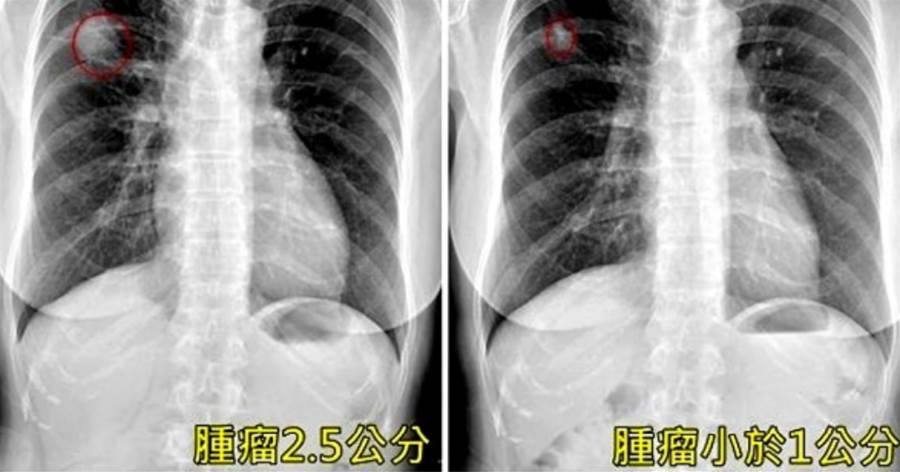

圖片來源:ETtoday